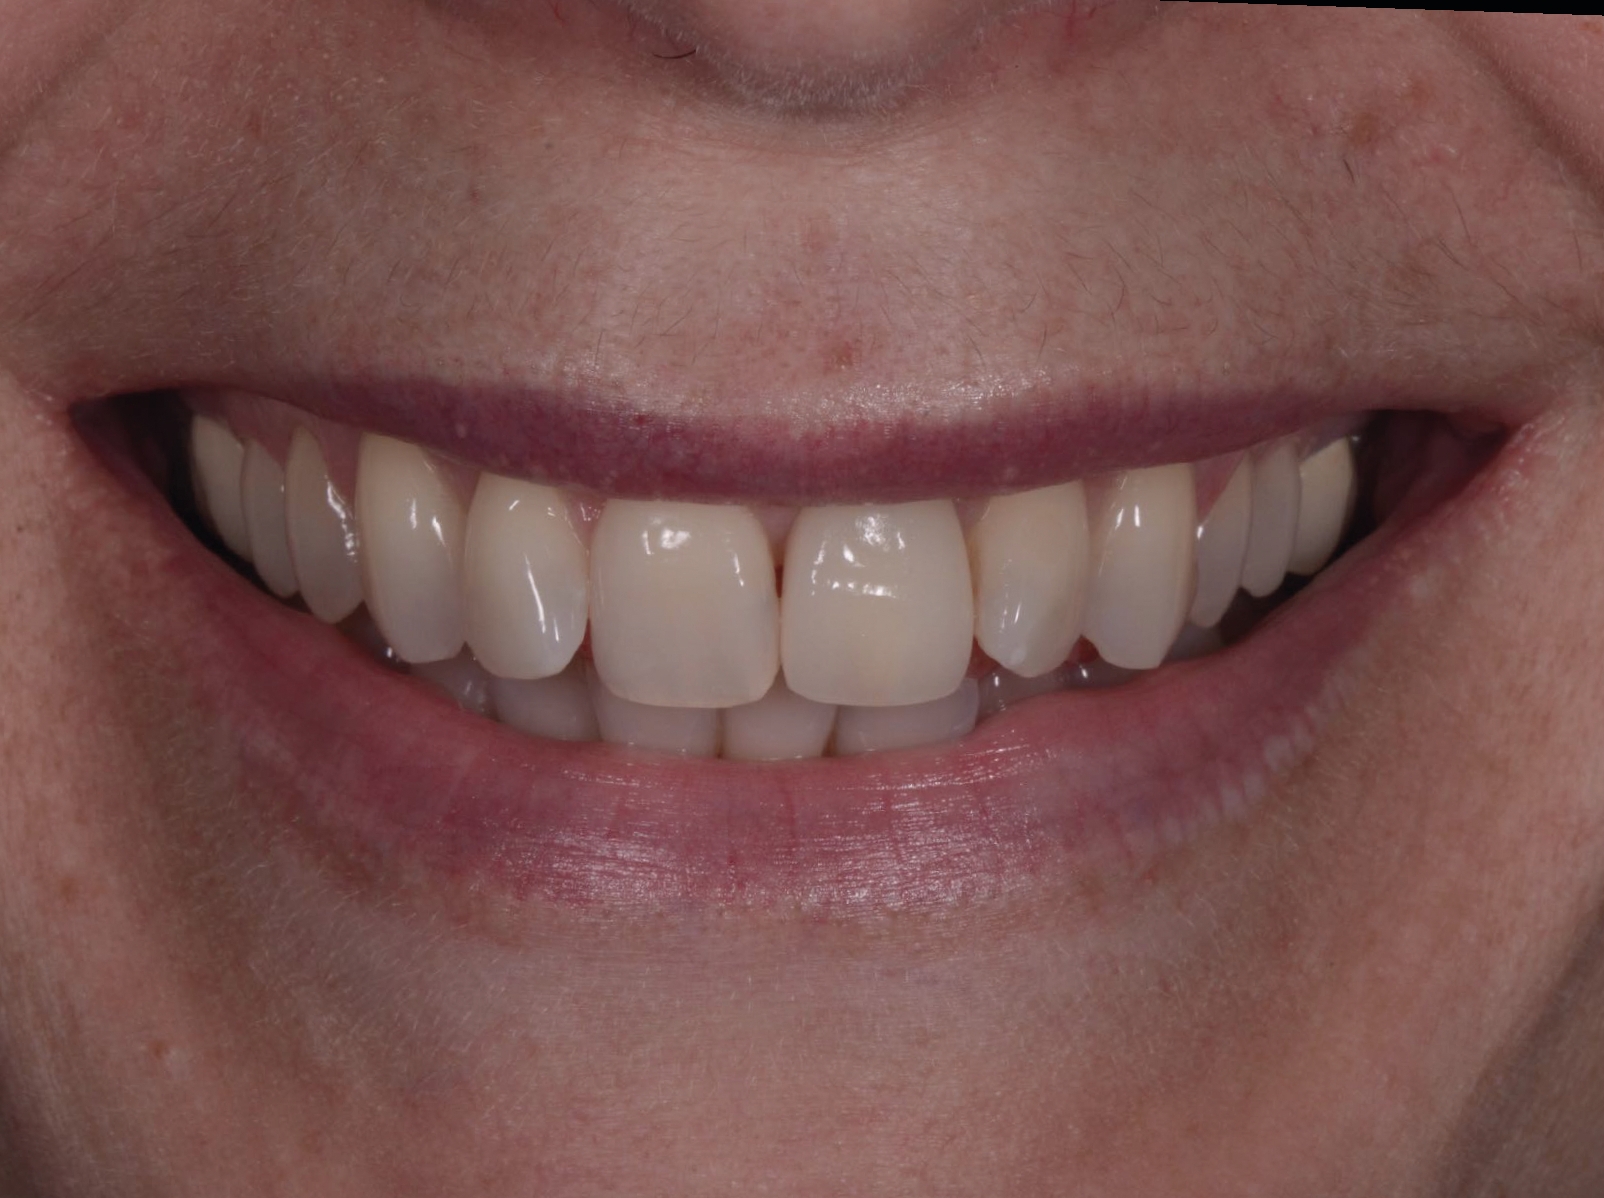

Fig. 20a : Couronne définitive implanto-portée, vue extraorale ;

Fig. 21a : Sourire avant le traitement.

Fig. 21b : Sourire après le traitement.

Lors du suivi a cinq ans, on ne peut que constater le résultat esthétique maintenu (Fig. 21). La radiographie montre un niveau osseux stable et une connexion étroite entre l’implant et le pilier (Fig. 22).